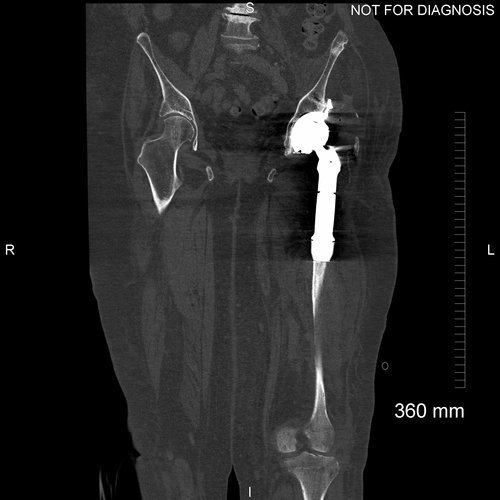

Stage two was carried out 11 weeks after the girdlestone procedure. A proximal femoral replacement and a custom 3D-printed trabecular titanium acetabular component were implanted.

Anteroposterior and lateral plain radiographs showing good bony contact surrounding the acetabular component. All of the screws are optimally positioned. The proximal femoral replacement is now in situ.

Coronal CT scan demonstrating optimal positioning of the acetabular component.